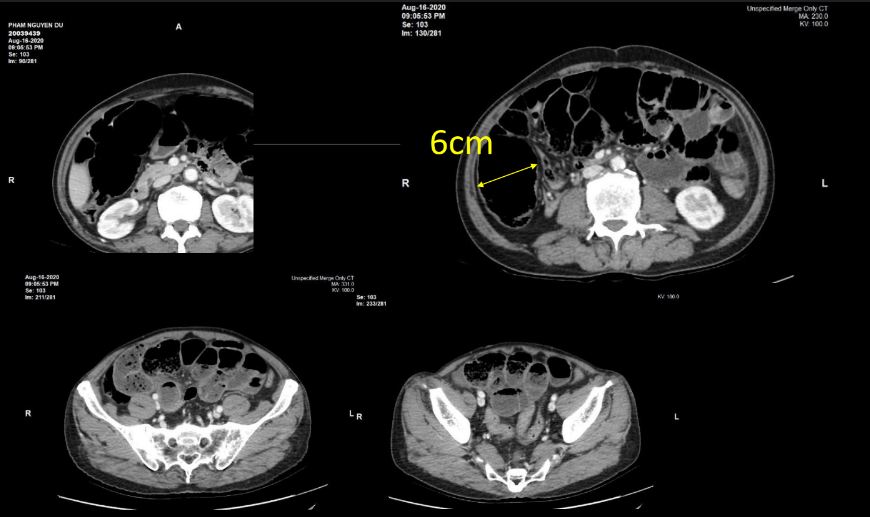

- BN nam 71T vào Vinmec cấp cứu lúc 23h30 (8/2020) vì đau bụng quanh rốn từng cơn, bụng chướng kèm bí trung đại tiện, nôn. BN đã vào BV huyện địa phương, chụp XQ bụng đứng có hình ảnh các quai ruột giãn + mức hơi-dịch. CT Scan bụng không thuốc (15h30 cùng ngày) nhiều quai ruột giãn chủ yếu 1/2 bụng phải.

- Xét nghiệm: Ure 9.1 Crea 105, GOT/GPT 21.0/24.9, D-Dimer 1007, WBC 18.600 (N90.5%), K+ 4.3, Na+ 139, Cl- 94.9 CT bụng (Vinmec):- Hình ảnh một số quai hỗng tràng và hồi tràng giãn, vài quai trong lòng chứa phân (dấu hiệu Feces sign), hình mức nước hơi không điển hình, không thấy rõ quai ruột giãn cạnh quai ruột xẹp, không thấy dấu hiệu xoáy nước. Đề nghị phối hợp thêm lâm sàng.

- Manh tràng và đại tràng ngang giãn trong lòng chứa nhiều khí và bã thức ăn (Manh tràng dãn 6cm, dãn các quai ruột non #3.5cm)

- Hiện không thấy hẹp tắc các ĐM, TM mạc treo tại thời điểm khảo sát.